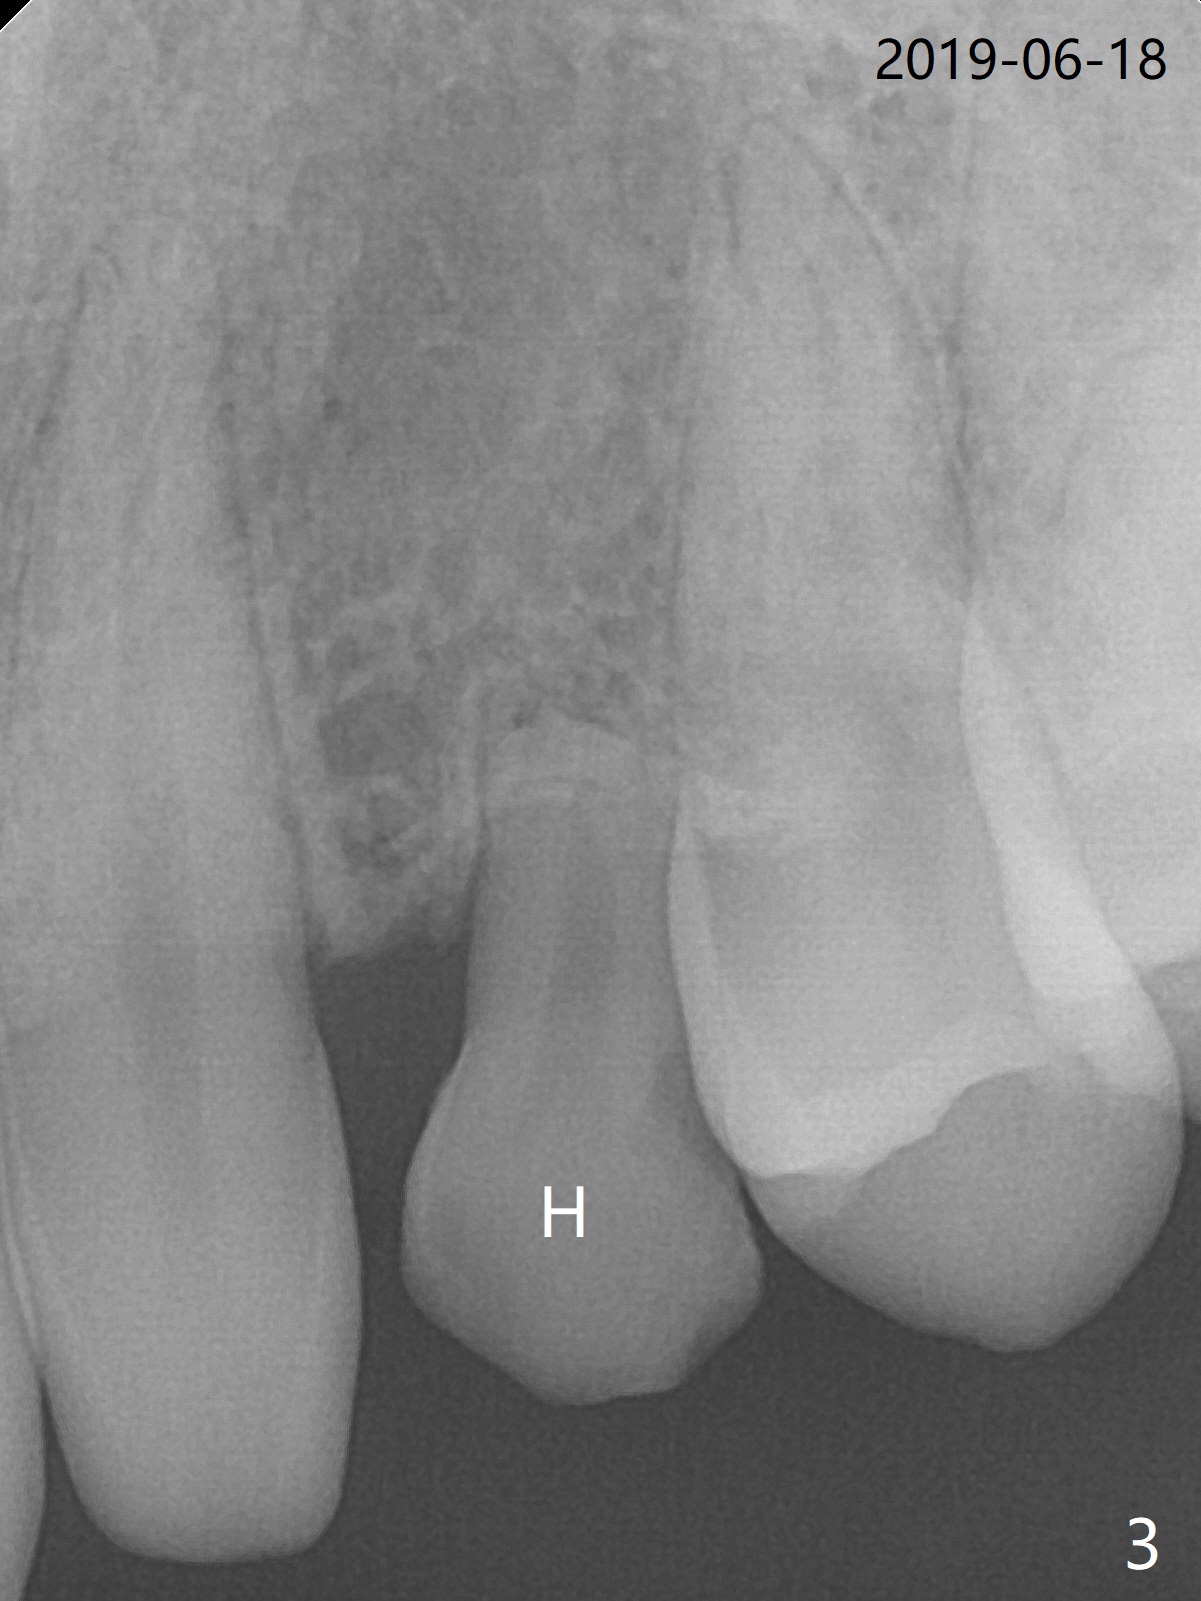

A 20-year-old man requests implant for the loose upper left deciduous canine. Pre-orthodontic panoramus shows 3 implants are needed (Fig.1). Post-ortho PAs indicate root resorption of the upper right deciduous canine as well (Fig.2,3). To reduce radiation, 5x5 cm CBCT is taken for the anterior maxilla, the 1st implant to be placed at #11 in the Thanksgiving this year, while the 2nd one at #6 early next January (Fig.4,5). 1-piece implants may simplify treatment.